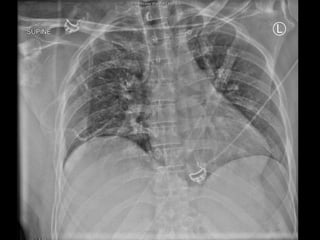

Resus

Intubation

Bilateral ICC’s

Right Lower Limb splint